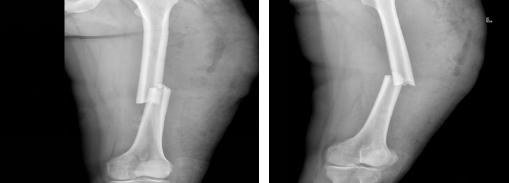

图3、4术前的DR检查

患者和家属了解到有省医院对口支援医师,在认同治疗方案和风险后要求支援医师主持手术。术中,姚豹医生凭借高超的手术技巧和丰富的手术经验,巧妙使用骨科“金手指”器械撬拨闭合复位股骨干骨折,在微创下达到了解剖复位有效减少了手术创伤、后期护理难度和患者痛苦,微创下手术复位成功。

图7、8术后复查DR 图9术后换药治疗